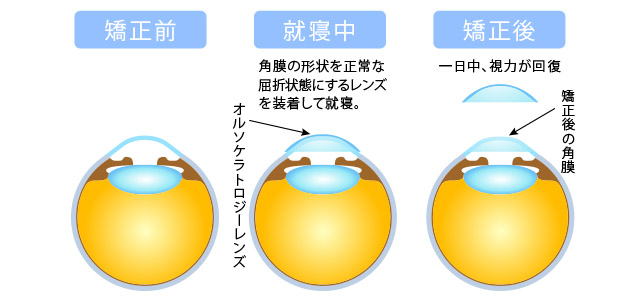

ホームページに必要な画像トレース及び、イラストのアレンジのご依頼。

ホームページに必要な画像トレース及び、イラストのアレンジのご依頼。